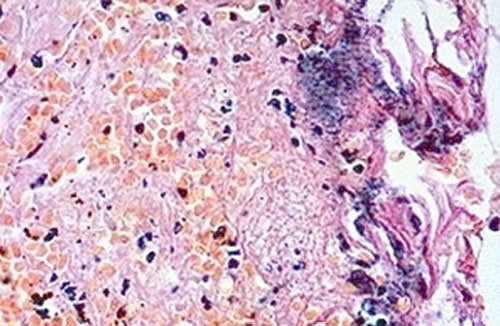

Figura 2

Infiltrado inflamatorio consistió en las células polimórficas, con la proliferación de fibroblastos y numerosos vasos sanguíneos. Mostraron los canales vasculares delgadas paredes cubiertas con tejido epitelial, con algunas zonas ulceradas cubiertas de fibrina.

Clínicamente, el Granuloma Piogénico (bucal) es un nódulo de color rosa o rojo que puede sangrar fácilmente con traumatismos menores. El examen microscópico reveló un infiltrado inflamatorio consistió en las células polimórficas, con la proliferación de fibroblastos y numerosos vasos sanguíneos 2,3,5,.Esta lesión es una de las más comunes y frecuentes encontradas en cavidad bucal, como lo reporta un estudio retrospectivo entre los años 2002 al 2006 y en el cual se determinó la prevalencia del Granuloma Piogénico y de otras patologías de la cavidad bucal 1, la muestra empleada fue de 309 casos; en pacientes de 0 a 99 años de edad de ambos géneros. Se calculó porcentajes de prevalencia de las lesiones y su distribución de acuerdo a la edad, género y localización; de ellos, 182 casos (58.8%) fueron diagnosticados como granulomas piogénicos, con una mayor prevalencia en la 2da y 5ta décadas de la vida con un 17.5%; el género femenino fue el más afectado, 120 (65.9%) casos, en comparación al masculino con 62 (34%). Las lesiones se ubicaron en el sector anterior, la extensión más frecuente fue en la mucosa masticatoria 1.